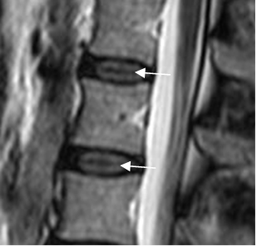

Fig 18. Hendidura intranuclear.

RM sagital en T2. Zona hipointensa central en el núcleo pulposo, que corresponde a la hendidura intranuclear central.

Fig 19. Degeneración del disco.

RM sagital en T2. Disco L3-L4 normal, con hiperintensidad del núcleo pulposo.

Los discos L2-L3, L4-L5 y L5-S1 son hipointensos, con pérdida de la diferenciación entre el núcleo pulposo y el anillo fibroso, por cambios degenerativos. (Flechas delgadas). Adicionalmente hay disminución en la amplitud del espacio L4-L5.